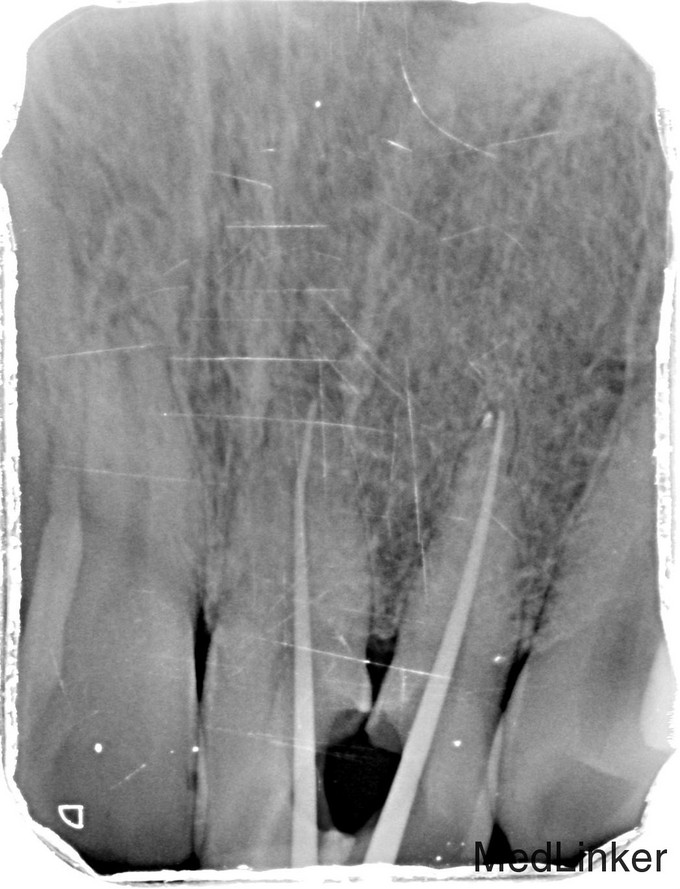

临床检查:21,22之间邻面龋坏,探(++),冷(++),叩(-),松动度(-),可探及穿髓点,无窦道,牙周红肿。 辅助检查:X线示21,22龋坏累积髓腔,根尖周牙周膜增宽。

诊断:21,22牙髓炎 治疗:经患者知情同意后,21,22局麻去腐,开髓拔髓寻找根管口,建立直线通路,扩通根管,确定工作长度。S3/EDTA凝胶镍钛器械,低浓度次氯酸钠冲洗根管,预备至30/06,试主尖X线示恰充,试干根管,导AH-PLUS糊剂,VDW热压胶垂直加压根充,术后见根管恰充,垫底树脂充填。调合术后24小时抛光。